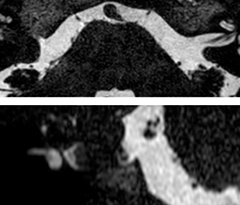

This is an example of acute ischemic stroke with distal occlusion of the right posterior cerebral artery. Note the improved visibility of the ischemic territory on the diffusion weighted image with high b-value. The 3D FLAIR shows a distal PCA occlusion. The fast SWIp depicts the thrombus on the isolated second echo image. The total scan time (including SmartBrain, preparations and a fast 3D T1w TSE Gd) is 8:00 minutes.